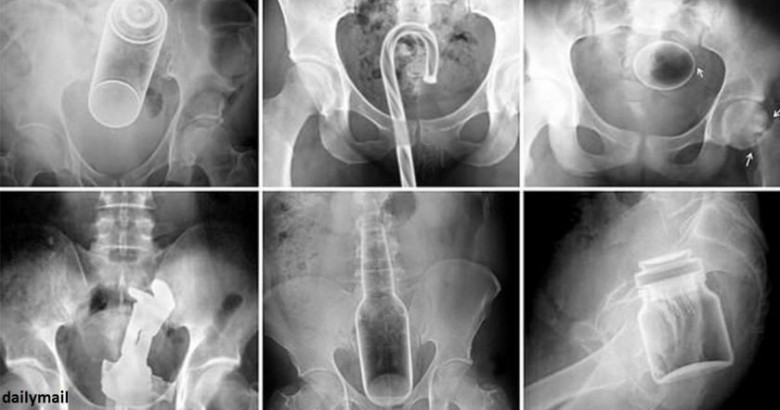

LifestyleԴանակ, պատառաքաղ, մանկական խաղալիքներ ու գարեջրի շշեր: Այս ամենն ինչ-որ ձևով կարող է հայտնվել օրգանիզմում: Այս նկարները նայելիս կարող եք համոզվել, որ այս կյանքում ամեն ինչ հնարավոր է: